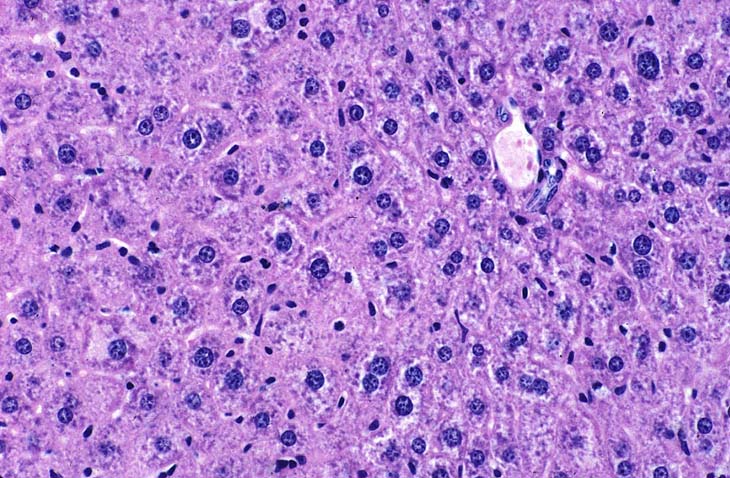

Polyploidy in the aged mouse.